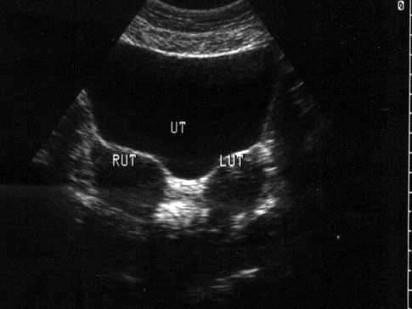

问题 患者女24岁,已婚未育,体检时B超发现如图所示,应诊断为 ( )

选项 A、双子宫 B、盆腔积液 C、左附件实质性包块 D、子宫肌瘤 E、右附件实质性包块

答案 A